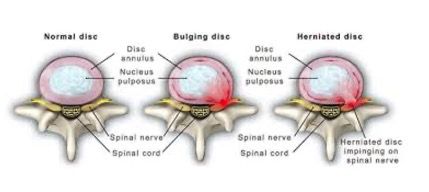

What are Disc Injuries?

What are Disc Injuries?

We have 23 discs in our spines from the top of our neck down to our low back. They are located between each vertebra. These discs have three main functions:

- To act as shock absorbers;

- Allow mobility in the spine; and

- To hold the vertebrae of the spine together and make space for the nerves to exit the spinal cord.

The discs work with the natural curves in our spines to reduce stress and pressure as you move. The disc has an outer fibrous tissue called the ‘annulus fibrous’. This surrounds the inner jelly like substance called the ‘nucleus pulpous’. The discs can become injured from the increased load. When this occurs, we see a bulging disc or herniated disc.

A bulging disc is where the nucleus pulpous bulges through the weakened annulus fibrous. This can put pressure on spinal nerves in the area and causes inflammation. Bulging discs respond well to Chiropractic care. Improving alignment and biomechanics in the area will help reduce the inflammation in the area.

A herniated disc is when the nucleus pulpous ruptures through the annulus fibrous from trauma or degeneration. This is more serious and causes severe pain and discomfort. A herniated disc will also often respond well to Chiropractic treatment.

When a disc bulges or herniates, it does not repair itself. The nucleus pulpous does not return to its original position. It is important to maintain correct spinal posture, keep hydrated, have good nutrition and maintain core strength through regular exercise to reduce the risk of a re-occurrence of symptoms.